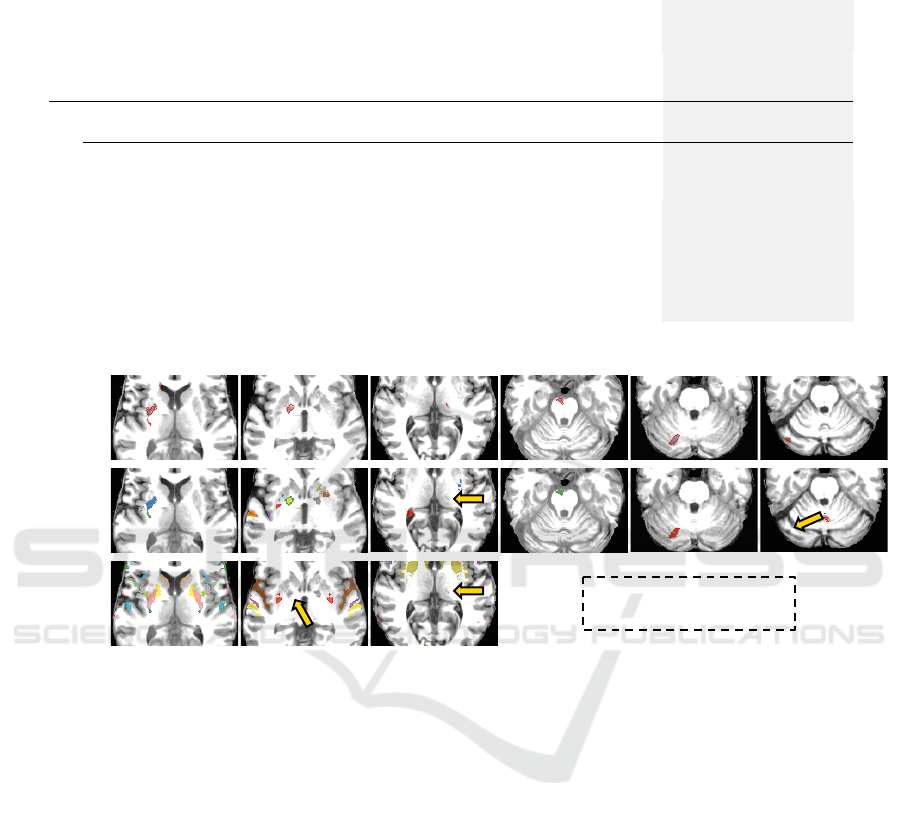

cerebellum and brainstem (detection rate of 0.6829).

Indeed, some lesions seems to be more challenging,

specially in the cerebellum, whose appearances are

similar to their surrounding tissues (Fig. 6, Image

6). However, its FP scores are similar to those of

hemispheric lesions which confirms the stability of

the method (compare rows 2-4 for BADRESC in Ta-

ble 1).